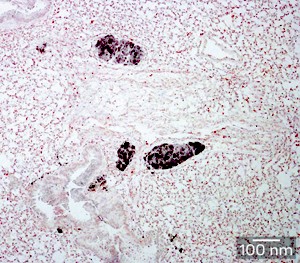

Fig. 1: Staining for cancer-specific antigen reveals colonies of disseminated tumor cells (dark spots) within the lungs of a 5-week-old RET.AAD mouse.

The SIgN-led team revealed the spread of cancer cells to tissues throughout the body in mice as young as three weeks of age. However, these early ‘colonies’ of disseminated tumor cells (Fig. 1) did not display the aggressive, invasive characteristics of true metastatic growths, suggesting that their progression was somehow being kept in check. Subsequent experiments demonstrated that this inhibition was largely due to the action of CD8+ T cells, and depletion of these immune cells from tumor-bearing RET.AAD mice led to rapidly accelerated tumor growth in the lung and reproductive tract.